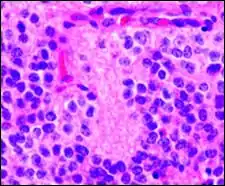

Perivascular pseudorosette

A perivascular pseudorosette consists of a spoke-wheel arrangement of cells with tapered cellular processes radiates around a wall of a centrally placed vessel. The modifier “pseudo” differentiates this pattern from the Homer Wright and Flexner-Wintersteiner rosettes, perhaps because the central structure is not actually formed by the tumor itself, but instead represents a native, non-neoplastic element. Also, some early investigators argued about the definition of a central lumen, choosing “pseudo” to indicate that the hub was not a true lumen but contained structures. Nevertheless, this pattern remains extremely diagnostically useful and the modifier unnecessarily leads to confusion. Perivascular pseudorosettes are encountered in most ependymomas regardless of grade or variant. As such, they are significantly more sensitive for the diagnosis of ependymomas than true ependymal rosettes. Unfortunately, perivascular pseudorosettes are also less specific in that they are also encountered in medulloblastomas, PNETs, central neurocytomas, and less often in glioblastomas, and a rare pediatric tumor, monomorphous pilomyxoid astrocytomas.[2]

Micrograph of perivascular pseudorosettes